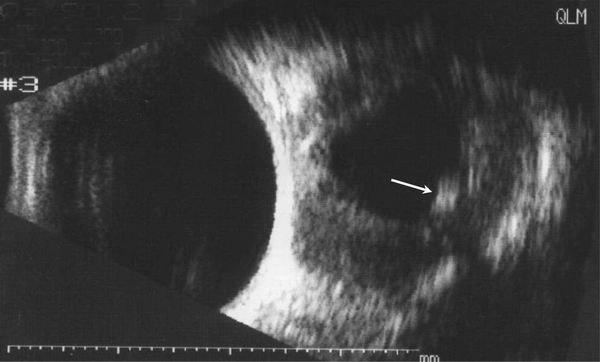

4.进一步检查 B超显示(如图):球后占位病变内有低回声,其内有强回声光点(囊虫,箭头)及筋膜囊水肿